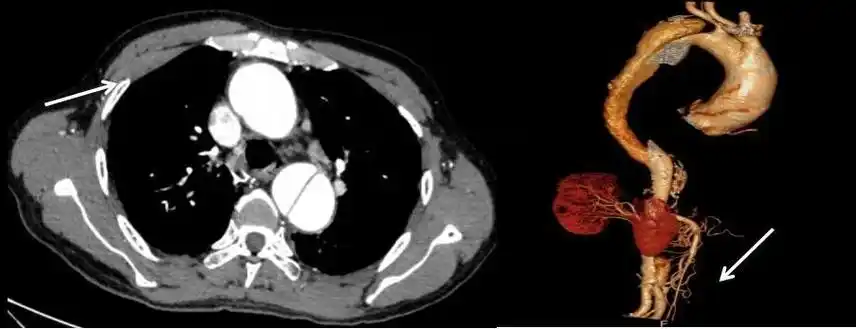

以腹痛为首发症状的主动脉夹层1例

在当地医院行强化 ct 显示胸腹主动脉夹层(stanford b型),而当地医院

夹层位于降主动脉时多表现为肩胛区疼痛,腹主动脉夹层形成可引起后背

主动脉夹层##腹主动脉瘤##第一血管